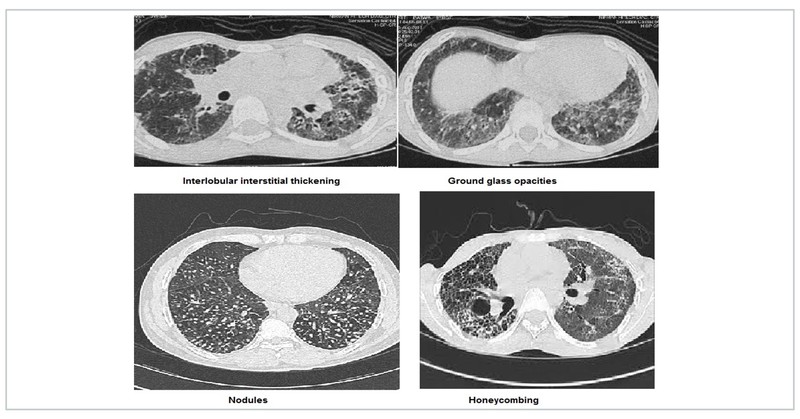

Interstitial lung diseases(ILD)

HRCT in ILD is an exhaustive topic in itself. ILD are characterised by interlobular interstitial septal thickening, honeycombing, ground glass opacification and nodules. Idiopathic interstitial pneumonia (IIP) have varied characteristic distribution. Atoll sign is defined as central ground-glass opacity surrounded by denser consolidation and is seen in COP. Sarcoidosis is characterised by fissural nodules and may cause tracheal nodularity. Miliary mottling with randomly scattered nodules in miliary tuberculosis, crazy pavement sign i.e appearance of ground-glass opacity with superimposed interlobular septal thickening and intralobular septal thickening, seen in pulmonary alveolar proteinosis and sand storm sign in pulmonary microlithiasis are some ILD mimics with characteristic CT pattern. The Head Cheese sign consists of juxta-positioning of distinct radiographic areas of low, normal, high attenuation is seen in sub-acute hypersensitivity pneumonitis, sarcoidosis and atypical mycoplasma pneumonias.